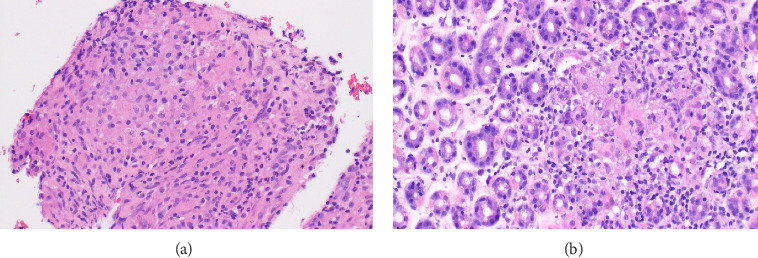

Background: Immune checkpoints are molecules that serve to augment or inhibit the immune response. The treatment landscape for numerous tumors now relies significantly on immune checkpoint inhibitors (ICIs). Pembrolizumab, a subset of ICIs specifically focused on the programmed cell death 1 (PD-1) molecule. By blocking PD-1, these inhibitors enhance the ability of the immune system to fight cancer cells. Although PD-1 inhibitors are critical in cancer treatment, their use can be associated with immune-related adverse events, such as ICI-related sarcoid-like reaction. Case Presentation: This report describes a 49-year-old female patient with stage IIIA breast cancer breast cancer who developed ICI-related sarcoid-like reaction after starting a neoadjuvant chemoimmunotherapy regimen that included Pembrolizumab. After 4 months of ongoing treatment, she started having significant nausea and vomiting. Computed tomography (CT) scans performed during hospitalization revealed multiple pathologically enlarged thoracic lymph nodes, suspicious for disease progression. Initially, the laboratory workup and cultures were unrevealing. However, esophagogastroduodenoscopy and bronchoscopy were performed, showing noncaseating granulomas in both the stomach and thoracic lymph node biopsy samples. The patient was diagnosed with a sarcoidosis-like reaction to Pembrolizumab. Notably, her symptoms rapidly improved upon initiating systemic corticosteroids. Follow-up CT scan showed a significant improvement in lymphadenopathy after discontinuing Pembrolizumab. Conclusion: This case emphasizes the significance of acknowledging sarcoid-like reactions as possible adverse effects of Pembrolizumab. Given the rising utilization of PD-1 inhibitors, it becomes imperative to be mindful of such adverse events. This awareness helps avoid misdiagnosing disease progression and aids in making informed decisions about ongoing treatment with ICIs.